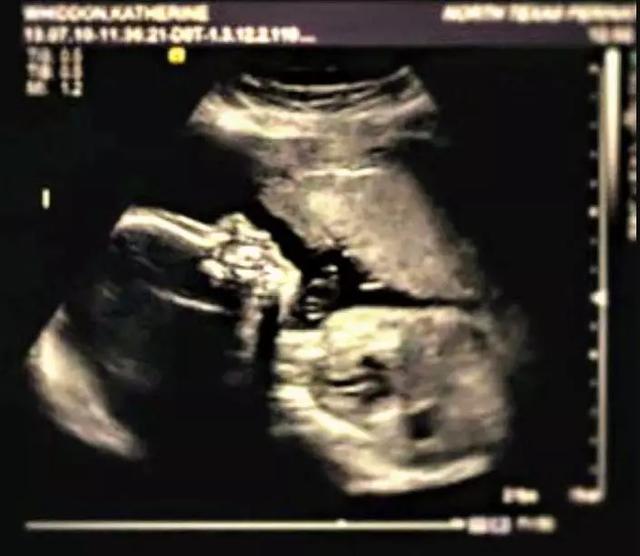

5月,怀孕第18周,她像往常一样去医院做了检查。

“是个男孩!”医生笑了,告诉她凯特笑得很开心。

但下一秒,医生面色铁青,有点犹豫地说:“恐怕情况有点不妙……”

“我看不见他的胳膊和腿……”

坏消息,凯特的宝宝天生残疾,很有可能活不长久。.